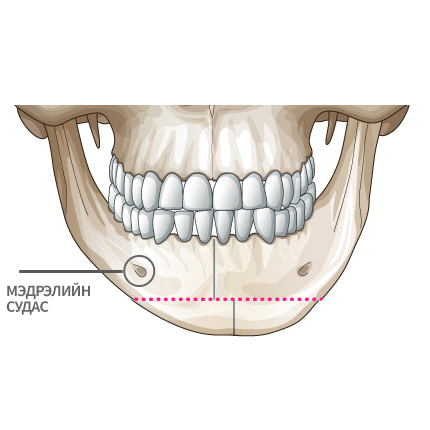

Mini V-line мэс заслын арга

Мэдрэлийн судаснаас зайлсхийж, эрүүний төгсгөлд зүсэлт хийнэ.

Ясны гол хэсгээс тайралт хийж авна.

Зүсэлт хийгдсэн эрүүний хоёр талыг нийлүүлнэ.

Эрүүний ясыг нийлүүлж тогтоож өгнө.

Хоёр хажуу талд товойж харагдах ясны хэсгийг тайрна.